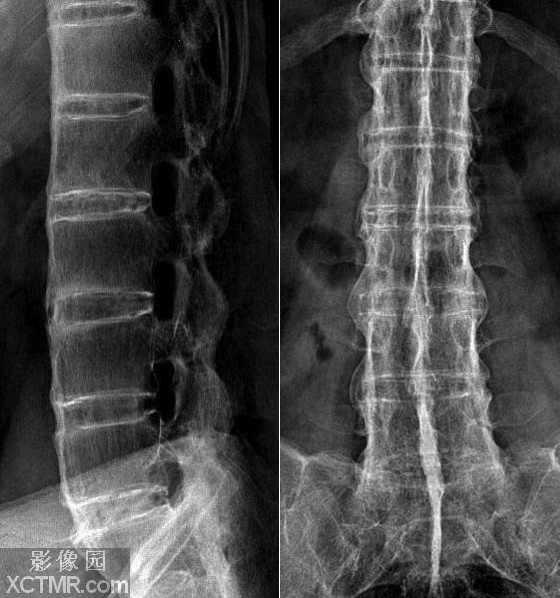

强直性脊柱炎这个疾病属于风湿的范畴,他的主要侵犯人的如骶髂和脊柱附着部位许多并发症,病症恶化会导致身体的许多地方,所以,除了强直的侵权关节病,也可以引起什么疾病?大多数因脊柱炎,几个月或几年前脊柱炎,一些患者还会出现一些变化如下,贵州强直专家魏琳琳介绍强直性脊柱炎的危害有什么